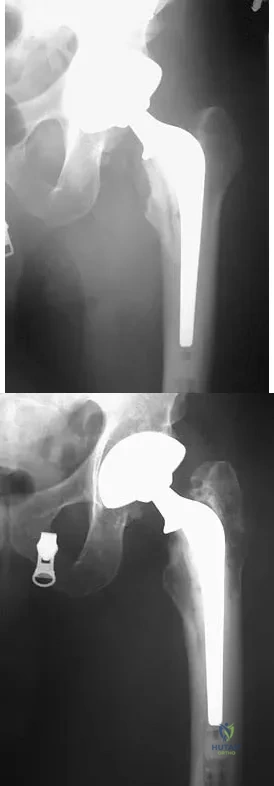

Question 34

A patient who underwent primary total hip arthroplasty 7 years ago that resulted in excellent pain relief and a normal gait now reports pain and a limp. Postoperative and current AP radiographs are shown in Figures 2a and 2b. What is the most likely cause of the pathology seen?

Explanation